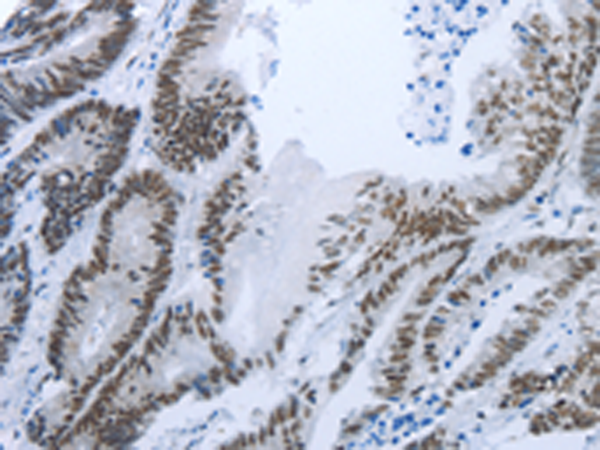

分类: 科研抗体货号: P11104别名: YC1, MSSP, SCR2, HCC-4, MSSP-1, MSSP-2, MSSP-3, C2orf12应用: IHC反应种属: Human, Mouse, Rat